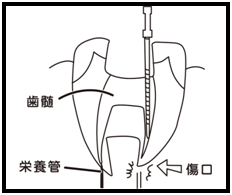

⑤ 次に、仮詰めをします。 虫歯が神経まで達して炎症を起こしているので、人によってはズキズキとした痛みを感じる方もいます(>_<)

虫歯が神経まで達して炎症を起こしているので、人によってはズキズキとした痛みを感じる方もいます(>_<)